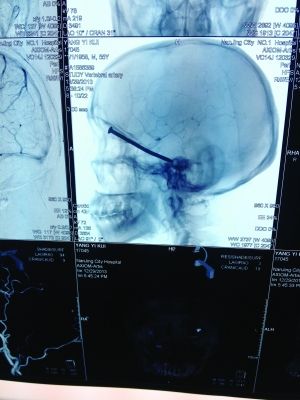

CT投影结果,把大家吓了一跳:杨先生脑子里居然有一根长钉,从眼眶一直“伸”到了接近后脑勺的位置!铁钉细长略带弯曲,长达8厘米。根据推测,铁钉应该是从上眼眶的缝隙中飞入,一直插进脑颅中,末端还有一个小小凸出的钉帽。

所幸避开了重要血管和神经

据南京市第一医院神经外科主任医师罗良生介绍,眼眶处虽然有骨头,但比较薄,如果钉子的飞行速度够快,就能轻易地穿透骨头进入头颅。“钉子进去后,可以看到它附近有很多重要神经和血管,比如视神经、颈内动脉,等等,一旦戳到任意一根,都会引起失明甚至大出血。而这根铁钉却避开了所有这些重要神经和血管,颅内也没有出血,这样的情况非常罕见,患者实在是太幸运了。”